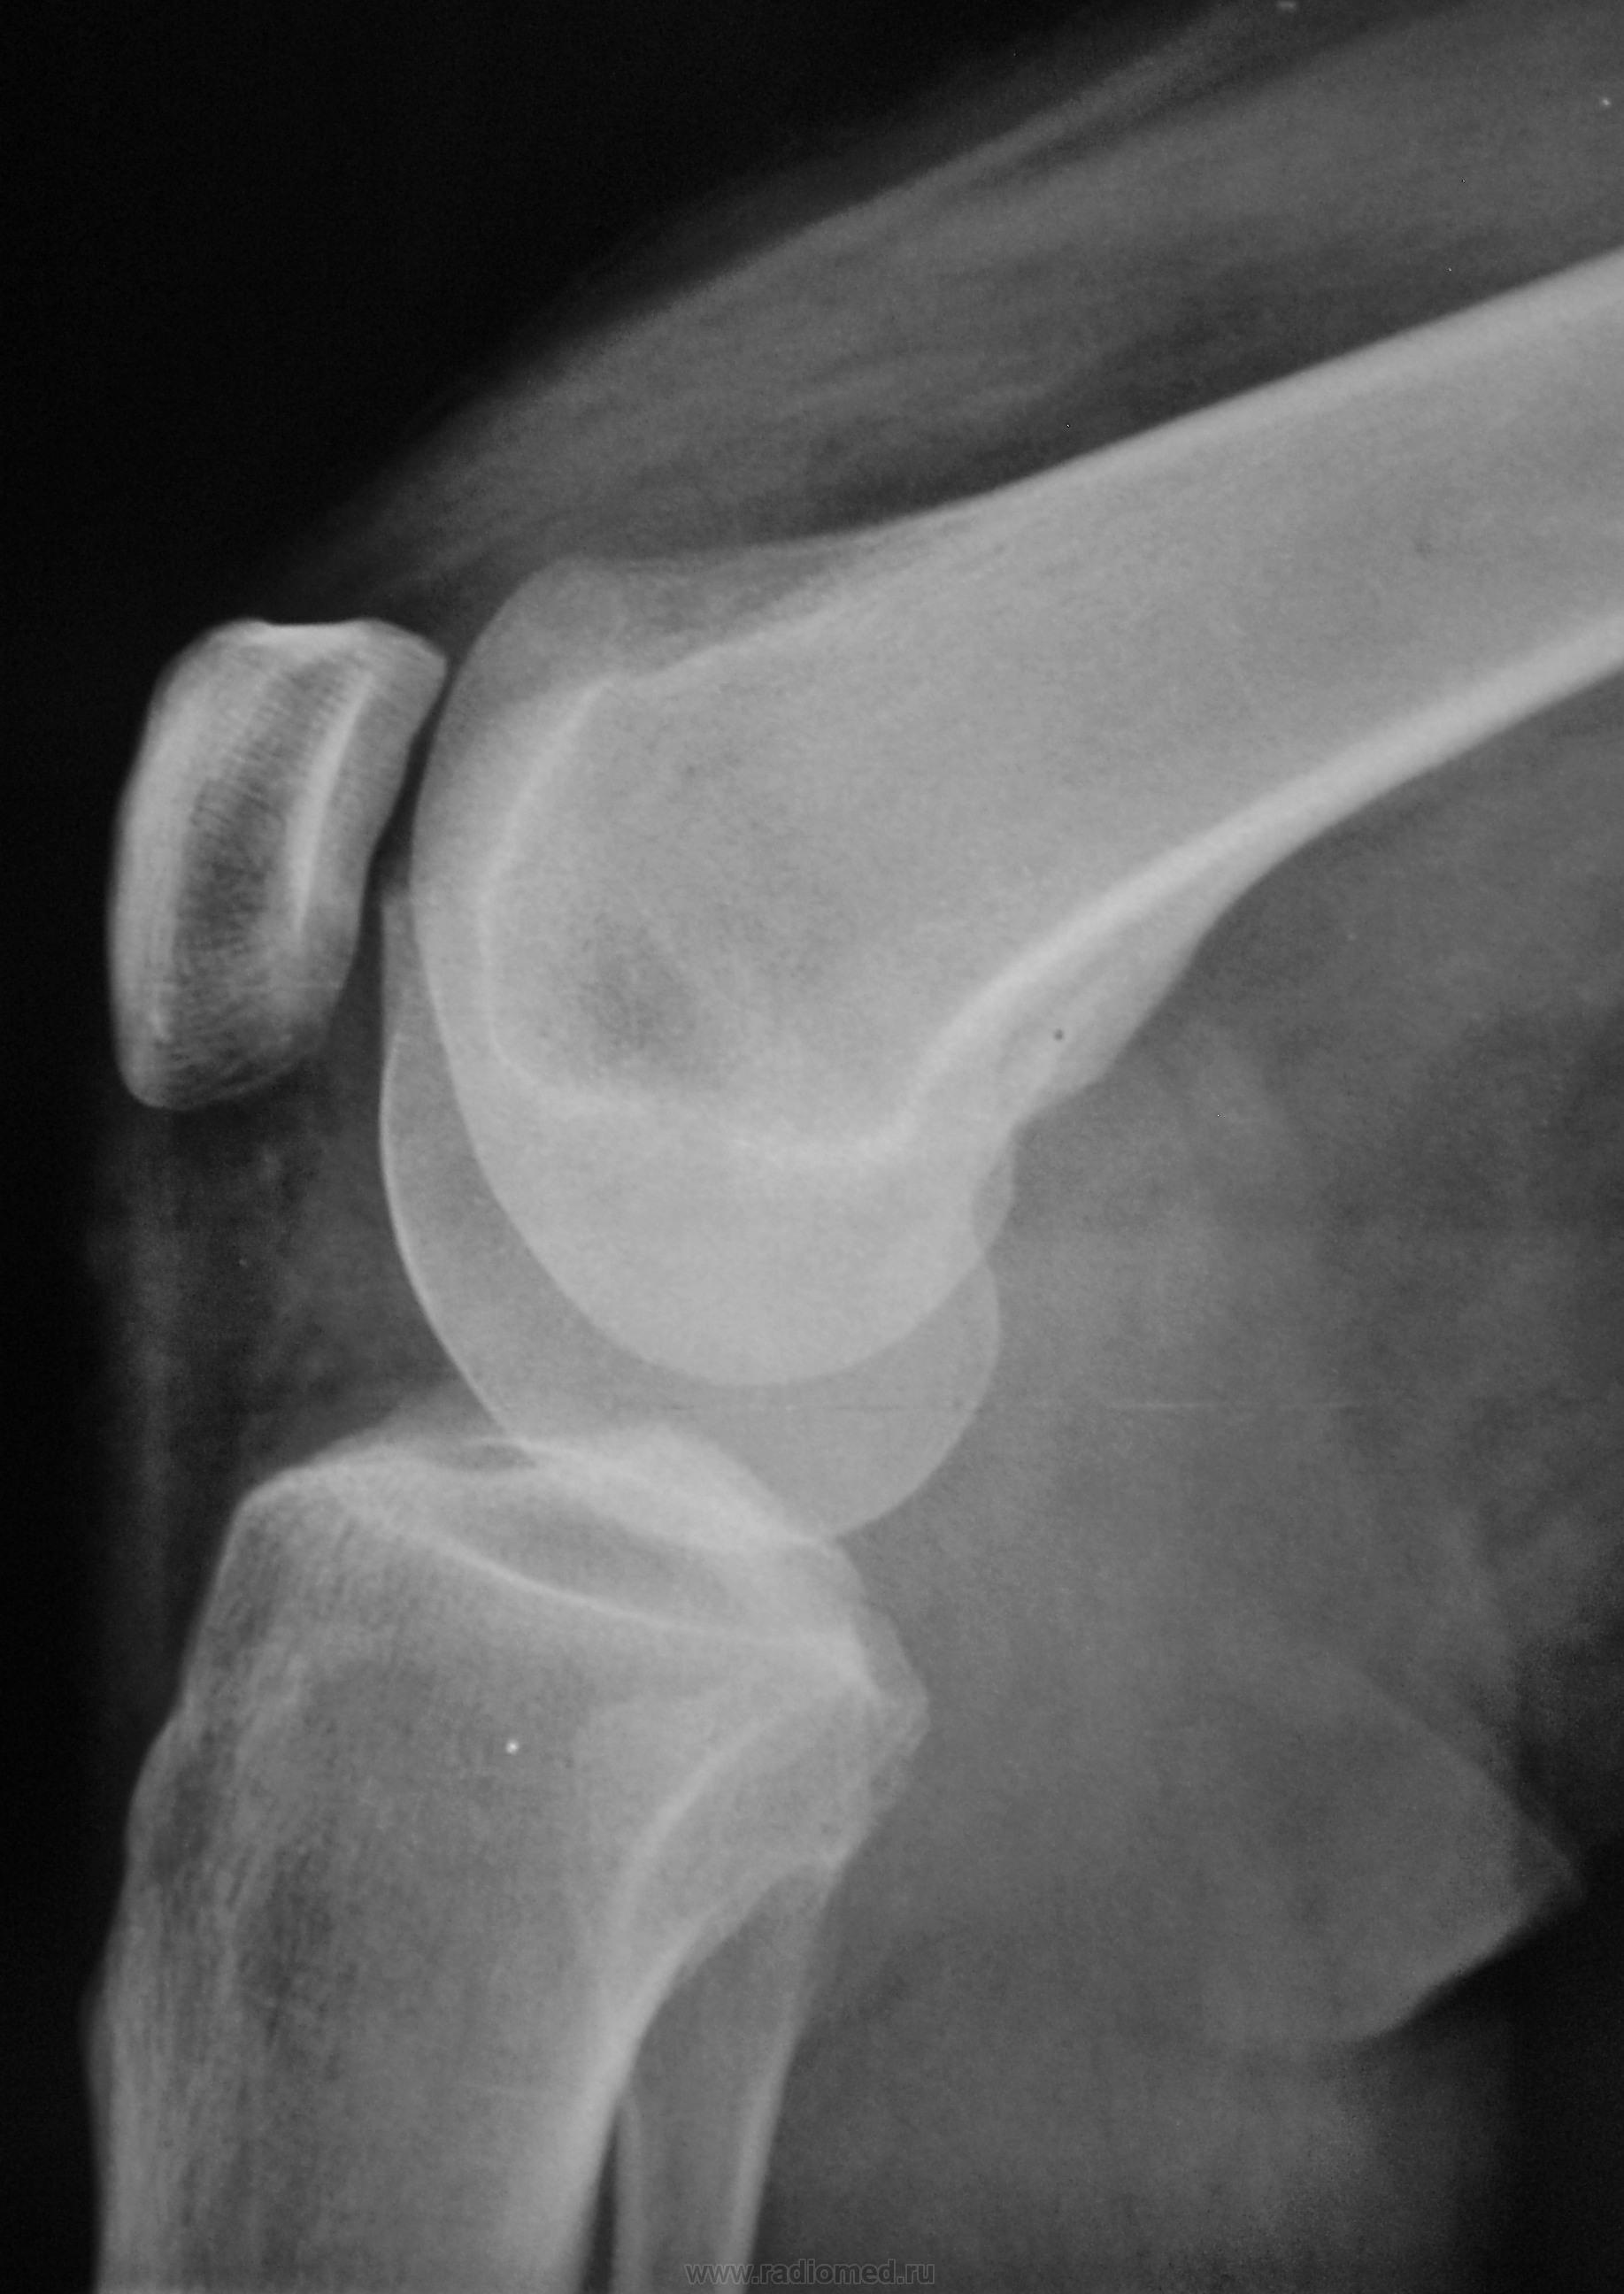

По поводу болей в коленном суставе пациент хирургом направлен на рентгенографию коленного сустава

Две мысли: 1) очаги просветления за счёт деструкции; 2) может быть фантазия, консолидированный перелом. Без томограмм не обойтись

напоминает абсцесс Броди. В диф. ряд поставил бы туберкулёзный остит.

Около 40 лет. Фиксация наличия болей пациентом около 3- мес.

или 3 месяца - подострый? локальный остеопороз без чётких контуров и периостальная реакция. о секвестрации язык не поворачивается сказать.

Перегрузочная болезнь осложненная неполным переломом б/б кости.